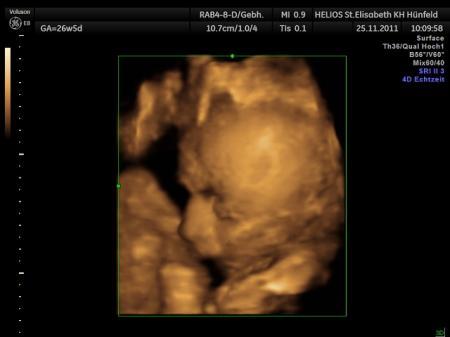

Bild zu